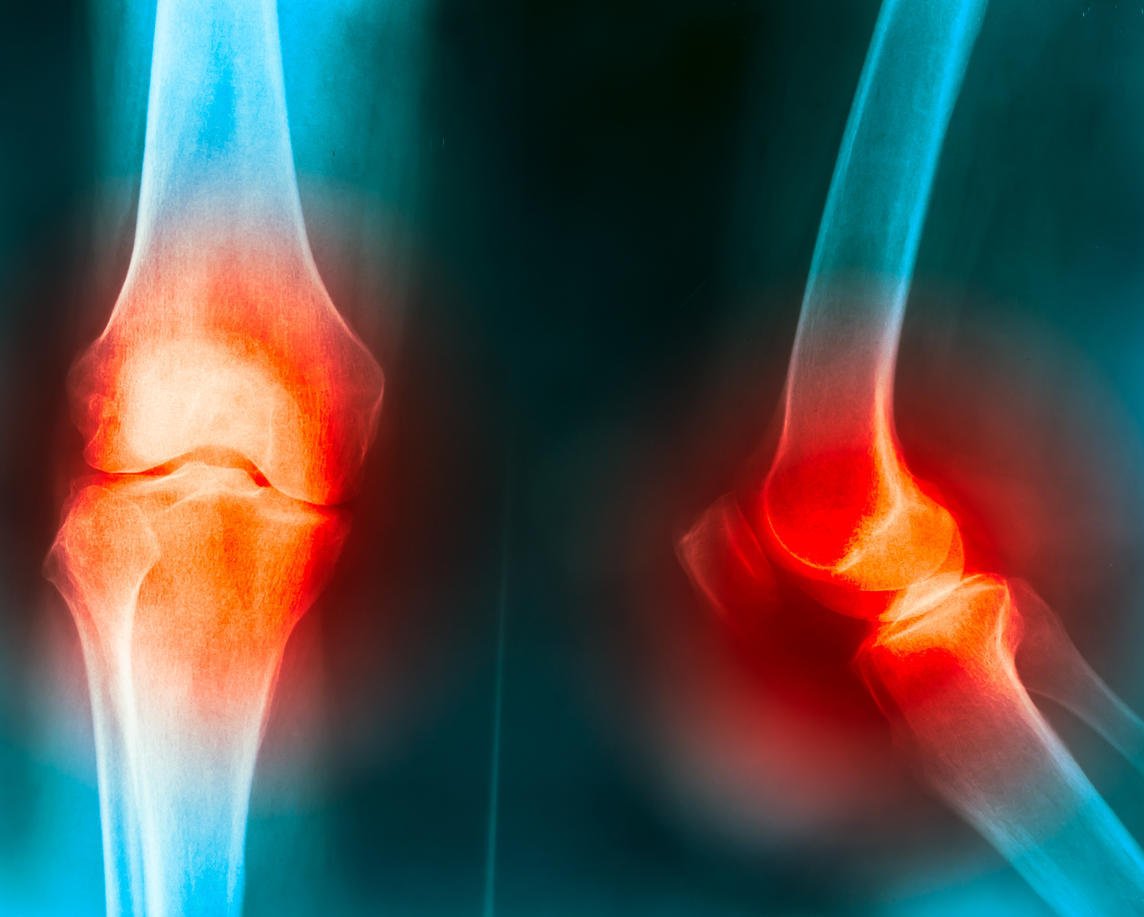

genou douleurs articulaires causées par le genou truma, la goutte, la polyarthrite rhumatoïde, l'arthrose du genou